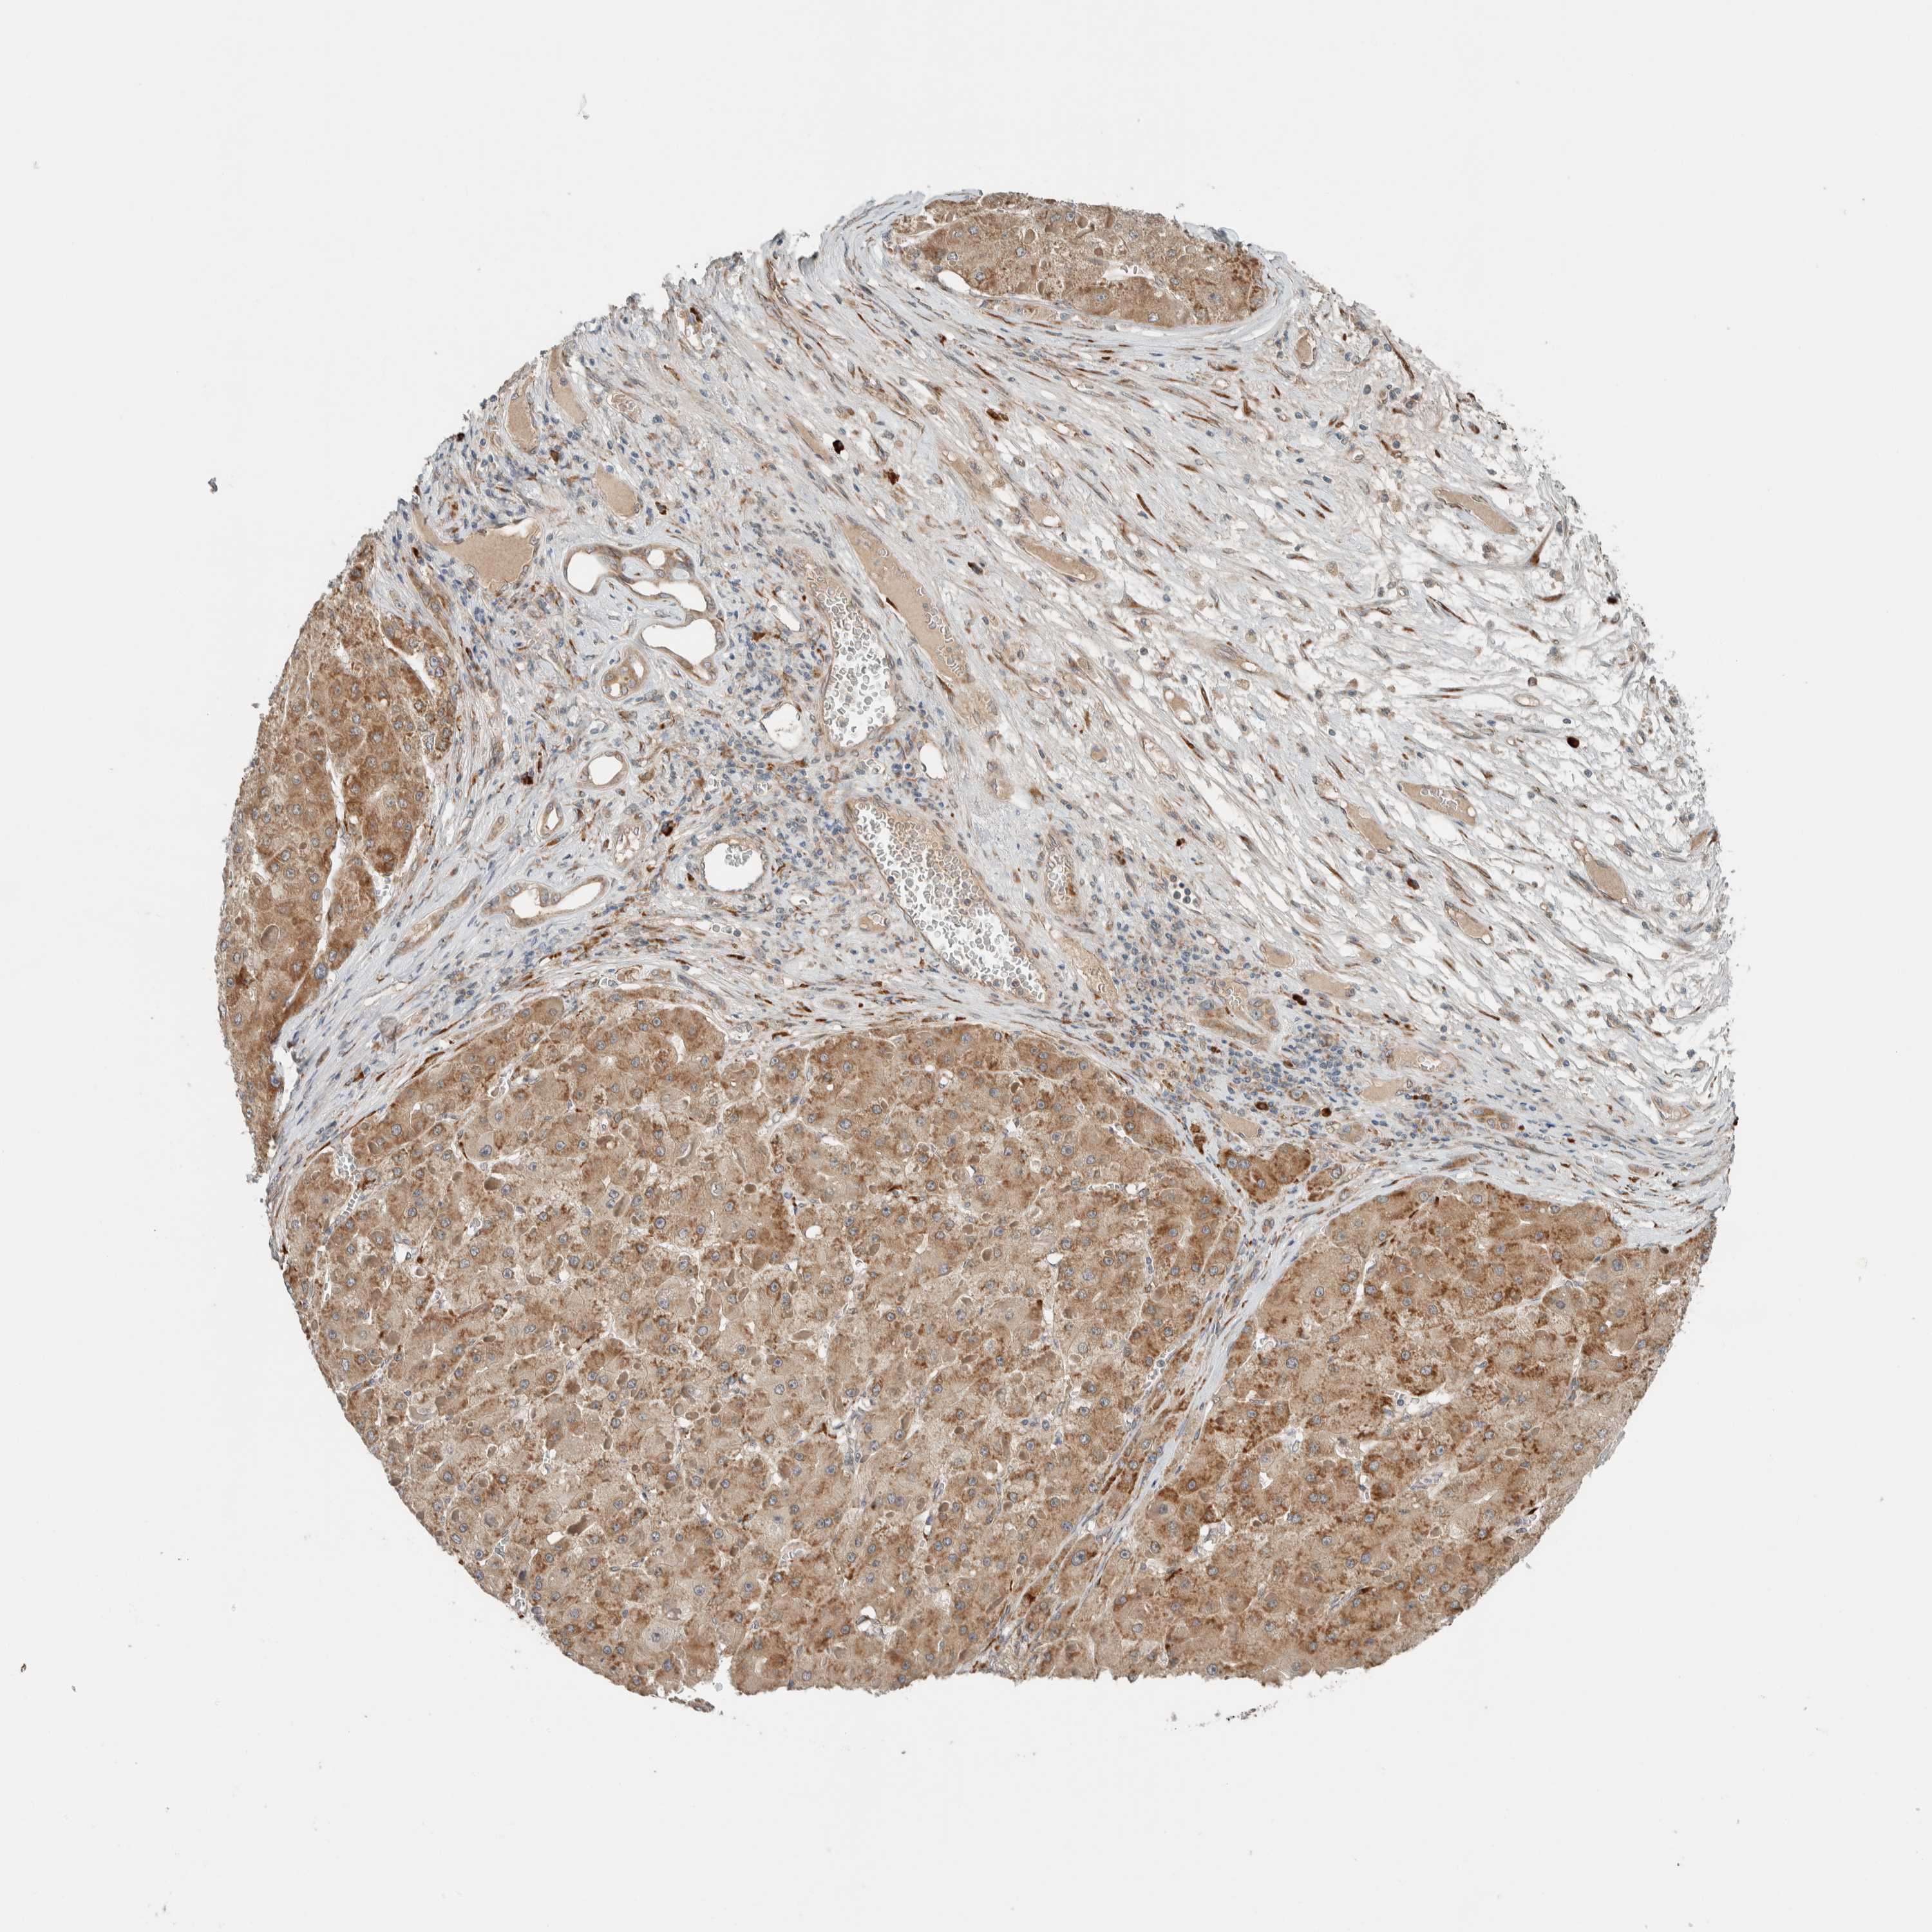

LIVER CANCER - Protein expressioni

A mouse-over function shows sample information and annotation data. Click on an image to view it in a full screen mode. Samples can be filtered based on level of antibody staining by selecting one or several of the following categories: high, medium, low and not detected. The assay and annotation is described here.

Note that samples used for immunohistochemistry by the Human Protein Atlas do not correspond to samples in the TCGA dataset.

Antibody stainingi

Antibody staining in the annotated cell types in the current human tissue is reported as not detected, low, medium, or high, based on conventional immunohistochemistry profiling in selected tissues. This score is based on the combination of the staining intensity and fraction of stained cells.

Each image is clickable and will lead to virtual microscopy that enables deeper exploration of all samples and also displays staining intensity scores, fraction scores and subcellular localization as well as patient and tissue information for each sample.

Antibody HPA023559

Antibody HPA023564

Antibody HPA044971

Antibody CAB031916

Staining

High

Medium

Low

Not detected

Intensity

Strong

Moderate

Weak

Negative

Quantity

>75%

75%-25%

<25%

None

Location

Nuclear

Cytoplasmic/membranous

Cytoplasmic/membranous,nuclear

Cholangiocarcinoma

Carcinoma, Hepatocellular, NOS